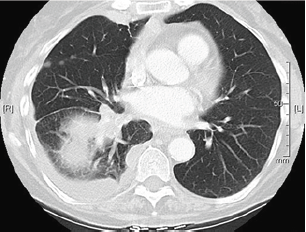

Figure 1:(before).

The patient's family history was significant for her biological father with multiple myeloma and the patient is a former smoker, who quit smoking 10 years ago. The CT scan of the chest with contrast was completed to check on the status of her lung cancer. Her CT scan of the chest (Figure 1) showed enlargement of the right lower lobe mass, soft tissue mass in the left atrium measuring 1.7 x 2.7cm, as well as enlargement of the right hilar node. It was noted that there was possibly a low-density mass within the pulmonary vein into the left atrium. Upon consultation with Cardiology and Oncology it was determined that there was no surgical option and anticoagulation was not recommended. She then continued to follow up with the Oncologist to discuss further chemotherapy (Figure 2).